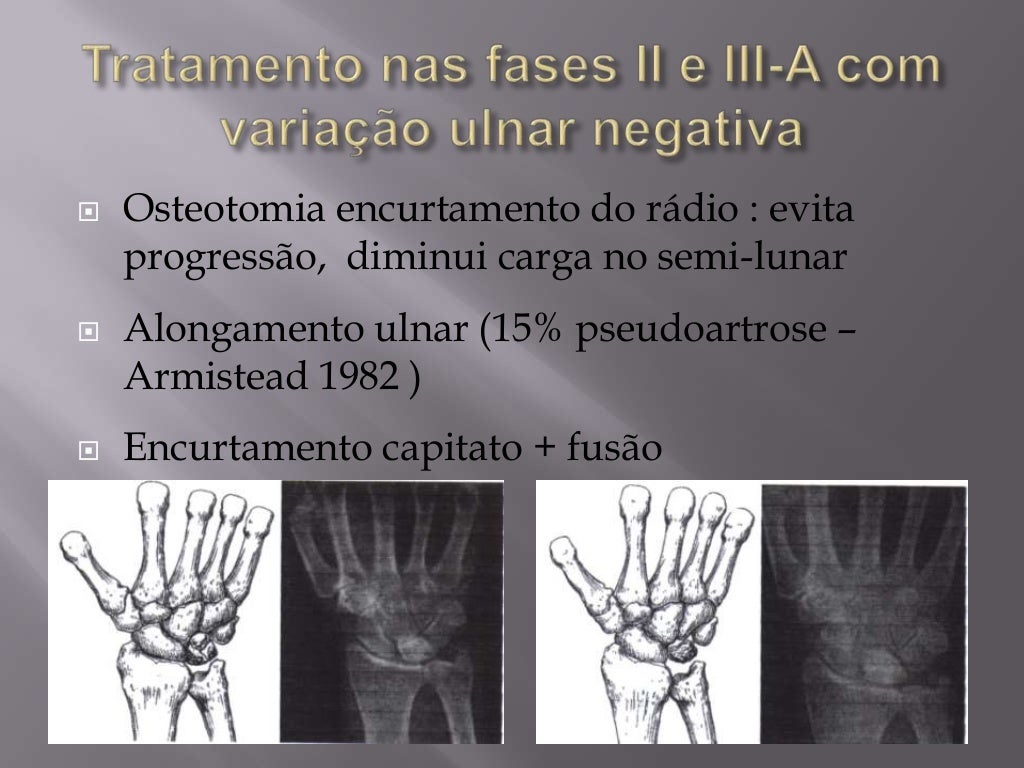

Objetivo: O tratamento da doença de Kienböck é desafiador, e a variabilidade dos resultados, apesar da técnica cirúrgica, mostra que deve haver outros aspectos que influenciam os desfechos. O objetivo deste estudo é determinar, por via artroscópica, o padrão de comprometimento dos ossos do carpo em pacientes com estágio 3 de Lichtman.

Kienböck's disease is likely an inflammatory, biological venous thrombosis disorder that leads to local damage due to intraosseous compartment syndrome. The basis of surgical treatment is to decompress the lunate to shield it from shear and compression loads. Existing osteotomy procedures will be described and compared to better understand.

Como funciona o tratamento da Doença de Kienbock? Basicamente, existem duas alternativas de tratamento para pacientes diagnosticados com a Doença de Kienbock, o tratamento conservador e o tratamento cirúrgico.Nos casos iniciais e nas primeiras visitas, o tratamento conservador é indicado, salvo quando o paciente já apresenta alterações estruturais graves e perda da altura do carpo.

Algumas das formas de tratamento mais utilizadas incluem: 1. Imobilização do punho. Muitos casos da doença de Kienbock podem melhorar apenas com a imobilização do pulso, pois dessa forma o osso é menos sobrecarregado, permitindo que a inflamação e a pressão no local diminuam. Para imobilizar o punho, o médico normalmente aplica gesso.